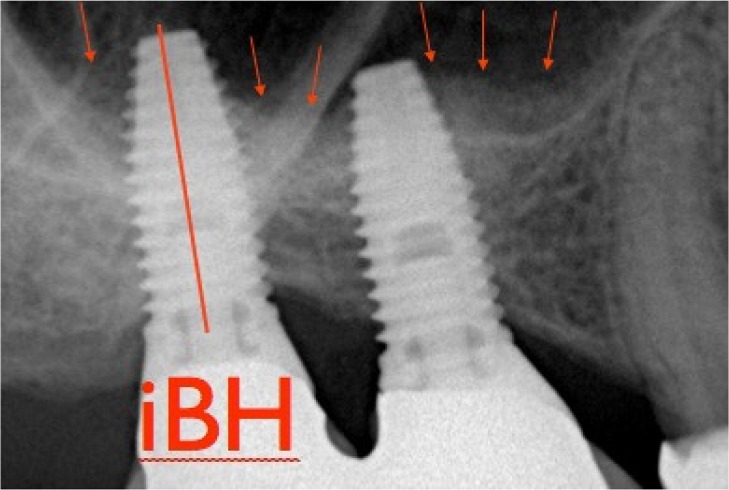

The marginal bone level changes were revalued annually using the intraoral radiographs taken with a parallel technique. The distance from the edge most coronal implant collar to the point of contact most coronal bone-implant was measured and compared with bone crest level. The values of the radiographic measurements mesial and distal were taken for each facility at the time of implant placement and then annually for a minimum of three years. The Marginal Bone Loss (MBL) for each interval was calculated by subtracting the Bone Crest Level (BCL) recorded at each followup visit by measuring BCL starting. X-rays have been used only orthogonal to record ABH. The increase of available bone [(Increased Height Of The Bone (IBH)] was calculated as the distance between the bone crest and the sign radiopaque more superior to the system, measured along the long axis of the implant (Figure 5).

Figure 5.

Postoperative periodical radiograph with IBH measurement (IBH = increased bone height).

In order to avoid distortions, bone increase was calculated as the difference between IBH and ABH.